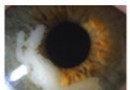

LASIK术后上皮植入临床

普通眼科资讯[临床精要][推荐]LASIK术后上皮植入临床研究佚名09-18